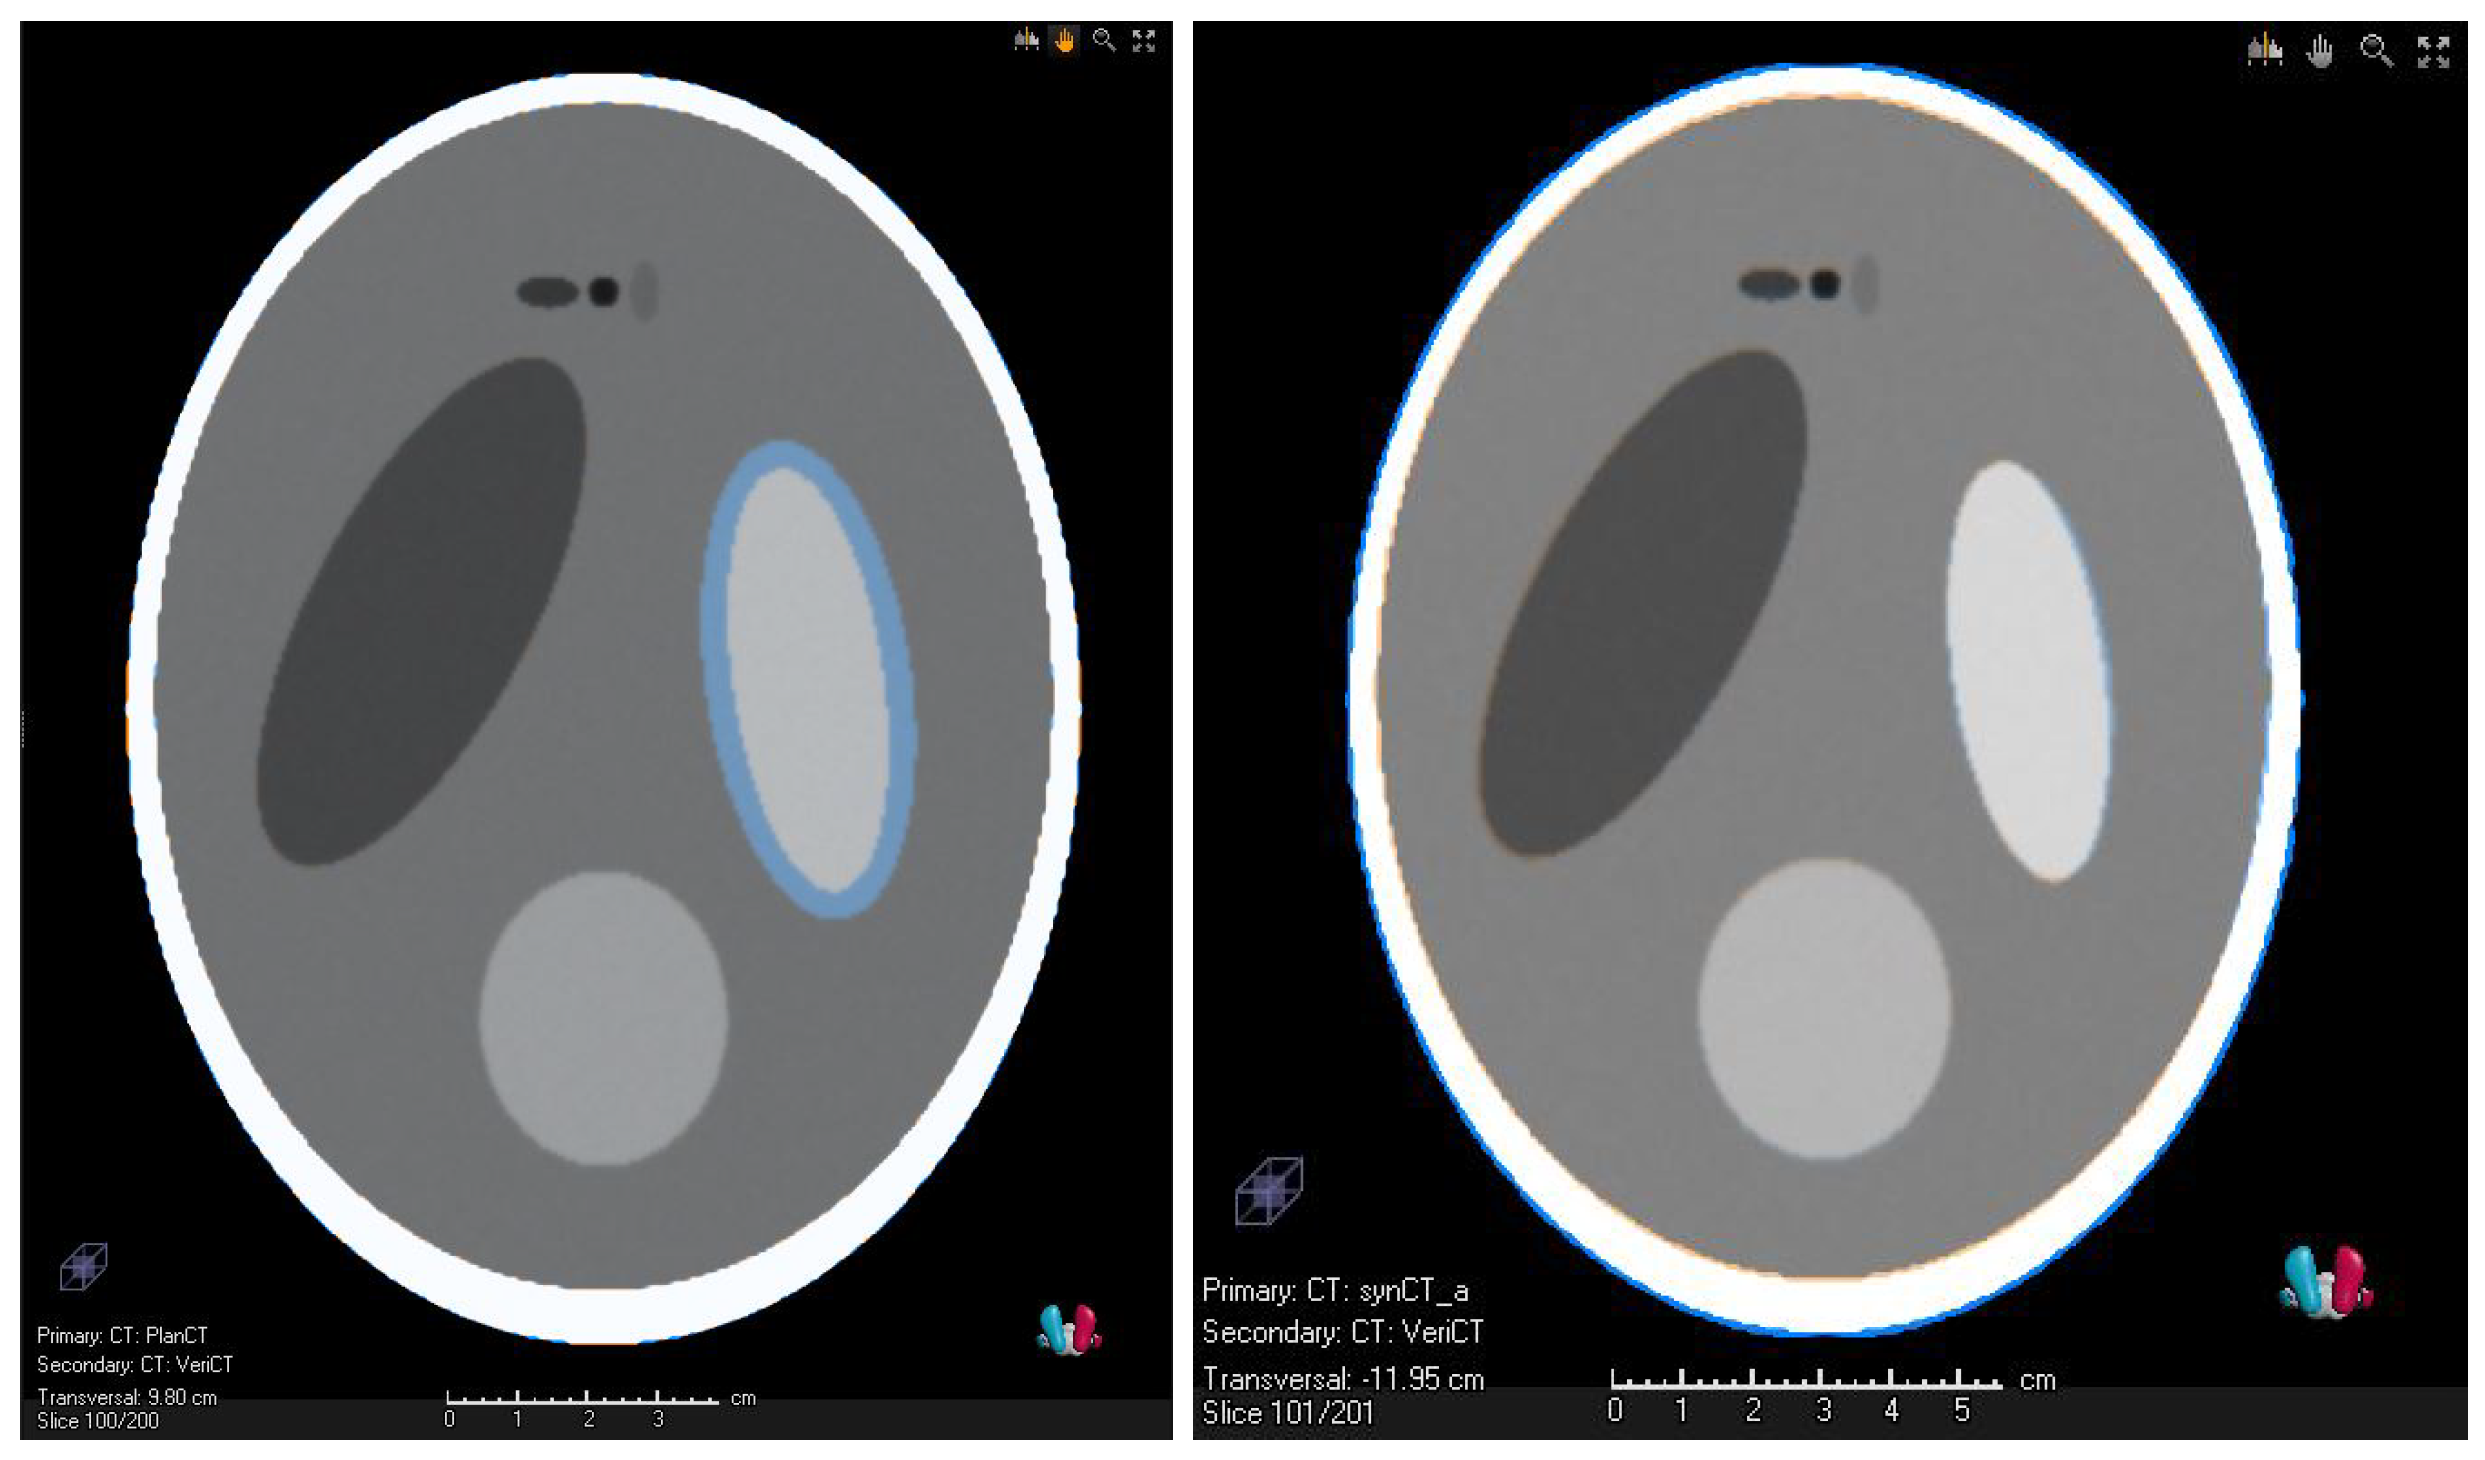

3.1. Validation of the Synthetic CTs—Results

3.2. Preliminary Results of the Clinical Study